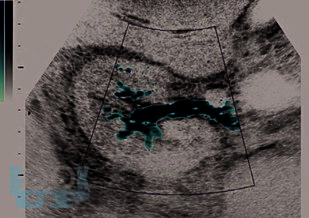

В основу монографии положены результаты собственных исследований и практический опыт авторов, использования ультразвуковых методов исследования мочевыделительной системы у тяжелой группы пациентов в промежуточном и позднем периодах позвоночно-спинальной травмы, проанализированы литературные данные отечественных и зарубежных авторов.

В монографии представлены современные методы комплексного ультразвукового исследования и патологические изменения мочевыделительной системы при позвоночно-спинальной травме. Описаны ультразвуковые симптомы поражения почек и верхних мочевых путей. Представлена разработанная авторами, эхосемиотика нейрогенного мочевого пузыря и эхосемиотика предстательной железы при позвоночно-спинальной травме. Описана технология проведения ультразвукового исследования у прикованных к постели и коляске, нуждающихся в постоянном постороннем уходе больных с последствиями позвоночно-спинальной травмы. Динамическое комплексное ультразвуковое исследование мочевыделительной системы позволяет осуществлять диагностику, мониторинг лечения и оценивать своевременность и эффективность урологического пособия пациентам, перенесшим позвоночно-спинальную травму.